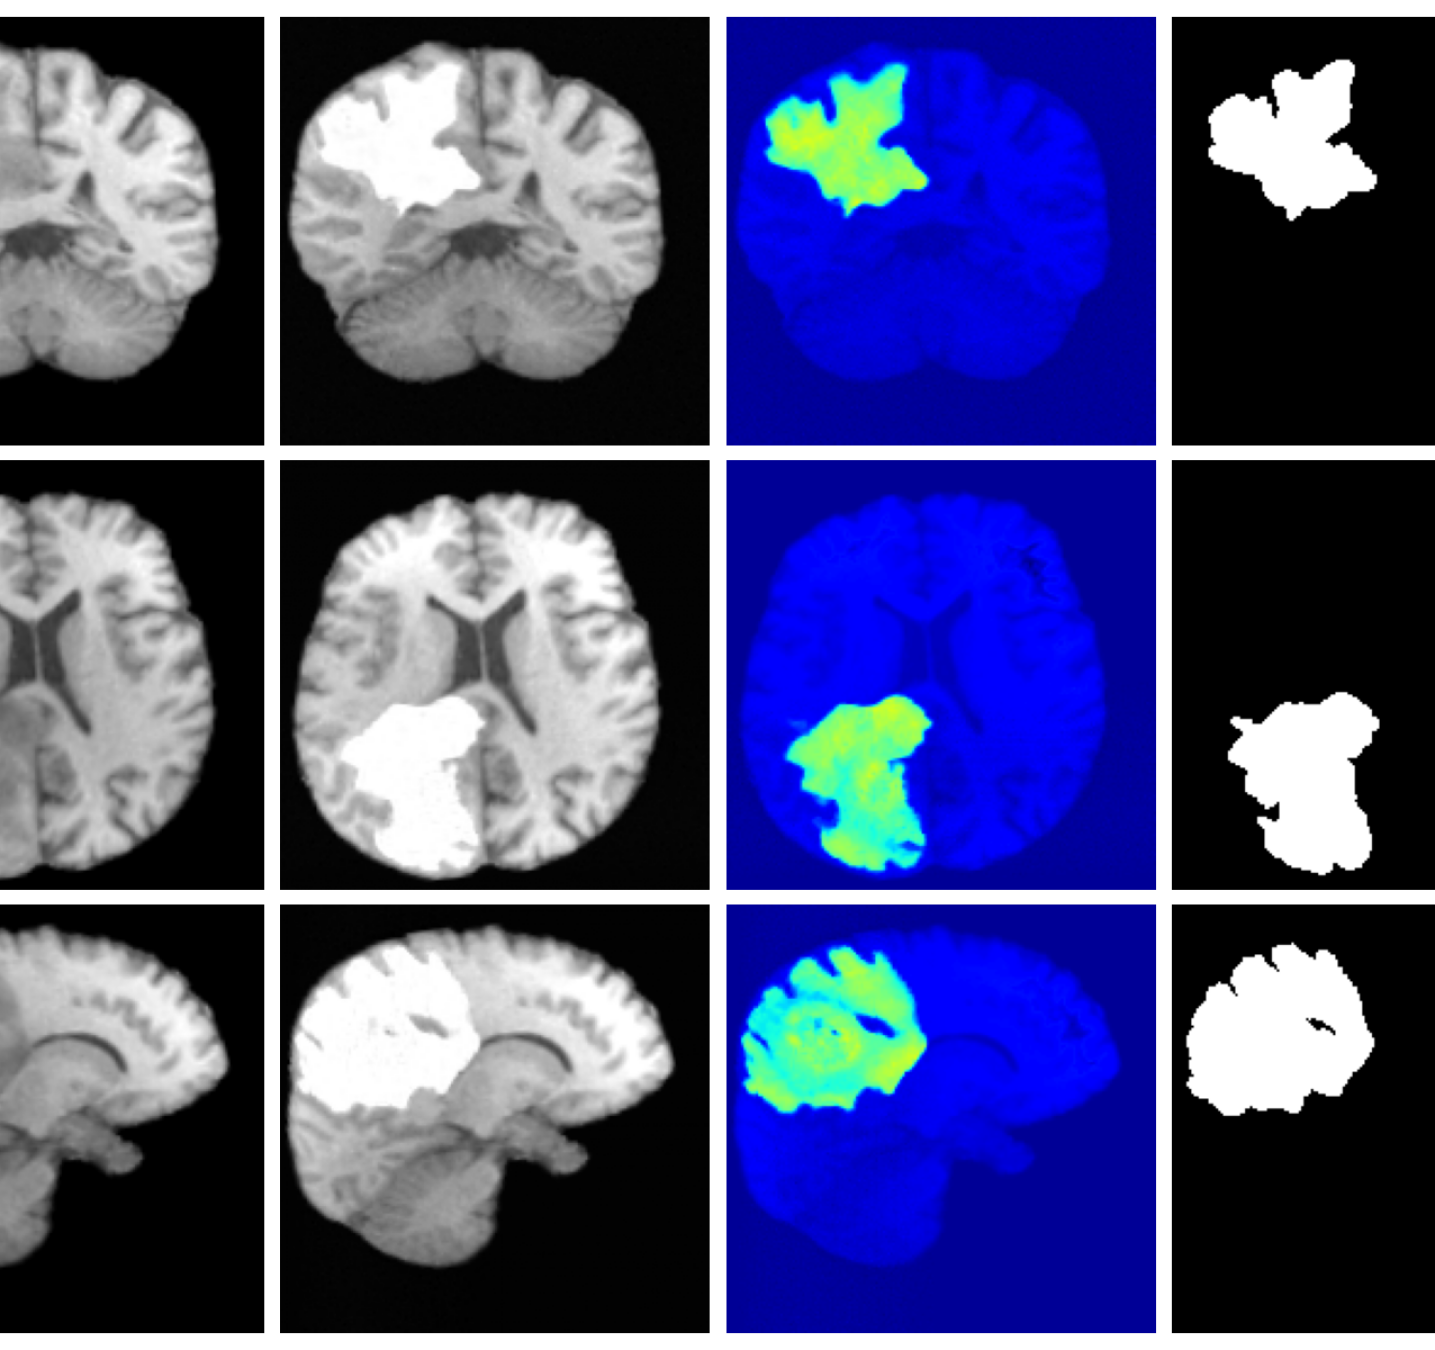

Figure 3 (additional examples in Appendix A.9) shows that SynthSR preserves healthy tissue but struggles with large lesions, while DDPM-2D and DDPM-3D, despite producing high-contrast anomaly maps, generate unrealistic homogeneous inpainting, consistent with their lower performance in Table 3. In contrast, our method yields the most anatomically plausible inpainted regions, although anomaly maps appear subtle due to low contrast between lesions and healthy tissue.

Image inpainting and refinement. We evaluate our inpainting approach on brain lesion datasets, where the goal is to reconstruct healthy tissue in regions affected by pathology. We conduct experiments on binary manual chronic strokes lesion segmentations and T1w images from the BraTS Baid2021 (N=398) and ATLAS Liew2017 (N=646) datasets. For the image refinement task, we first apply SynthSR to a subset of the ATLAS dataset and then apply our method with the forward model given in Equation 16 (=0.05, set heuristically) to refine the images.

For inpainting, the goal is to not only inpaint disease regions but also produce anatomically plausible reconstructions. We generate pseudo-healthy images for each method and evaluate them using two unsupervised anomaly detection models—a VAE Baur2020 and an LDM Graham2023b with pretrained weights from lawryaguila2025. Successful inpainting should yield pseudo-healthy images within the natural variation of healthy anatomy, resulting in minimal detected anomalies by the anomaly detection methods. For each model we compute anomaly maps, we report MAE, LPIPS, and the maximum Dice for the respective method between the anomaly map and segmentation; here, lower Dice scores indicate effective removal of disease-related anomalies.

Inpainting. To assess our anomaly inpainting performance, we compare to SynthSR as well as two recently proposed diffusion model approaches; DDPM-2D durrer2024b and DDPM-pseudo3D Zhu2023. All baselines use paired images and segmentation maps during training.

4.3 Image inpainting results

Inpainting results are given in Table 3. Our method achieves the best overall performance, attaining the highest rank on both datasets. For ATLAS, our method outperforms all baselines with improvements of 39.2% (VAE), 8.3% (VAE), 2.7% (VAE), 44.2% (LDM), 19.0% (LDM), and 51.4% (LDM). On BraTS, it improves over the best baselines by 25.6% (VAE), 5.2% (VAE), 27.4% (LDM), and 15.2% (LDM), while remaining competitive on the remaining metrics.